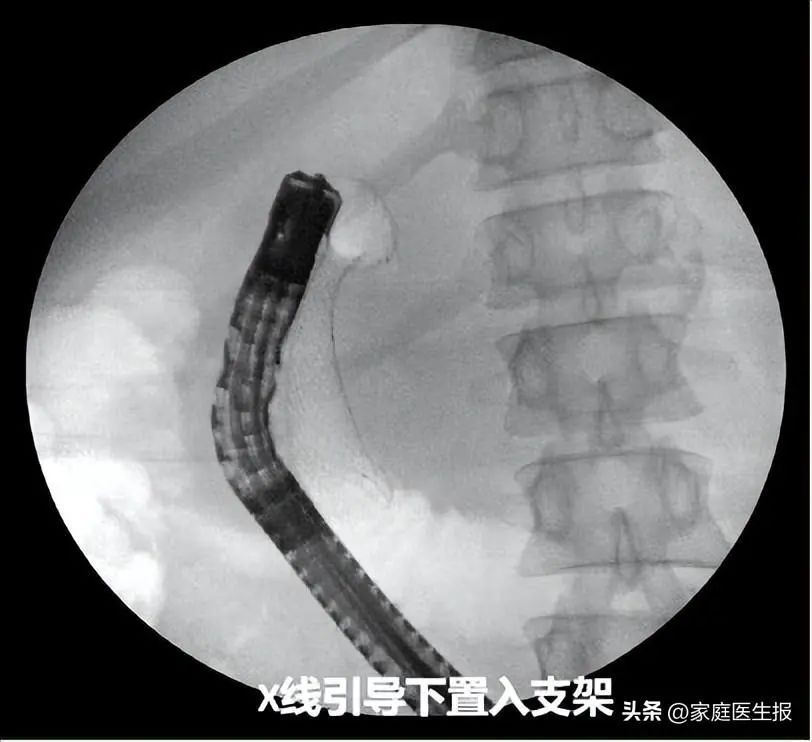

术中,熊光苏带领团队首先通过球囊扩张狭窄变形幽门部,进入十二指肠球部发现肿瘤已浸润导致管腔狭窄。直视下运用取石球囊带导丝越过狭窄段,注入造影剂肠腔显影,球囊打开后回拉至狭窄处,明确狭窄段长度。X光引导下成功置入长度60mm、直径26mm的金属支架,整个过程仅耗时15分钟。